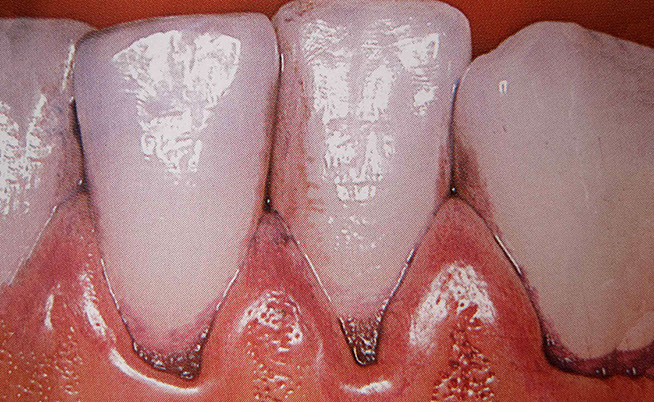

Before the actual cleaning, a detailed dental status is recorded. A staining solution is often applied to make hidden plaque visible to the patient. We are happy to take intraoral enlargements (photographs) for our patients to motivate them and to show concealed problem areas. You can only see what you know.

Finally, all tooth surfaces are coated with fluoride varnish for better protection against caries. The fluoride hardens the enamel and protects the tooth against bacterial acid attacks. This reduces the risk of tooth decay and remineralises pre-existing minor decalcifications of the enamel surface.